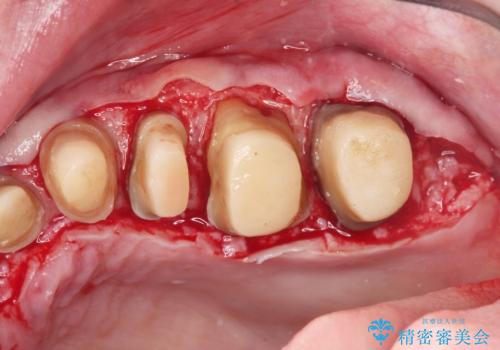

虫歯の徹底的な除去やセラミック補綴、精密根管治療、歯周外科を行うことで、治療後に歯磨きがしやすく、かみやすい機能的な仕上がりへと導きます。

歯周外科手術をおこなったことでフェルールも獲得でき、破折リスクをより抑えることにも成功しています。